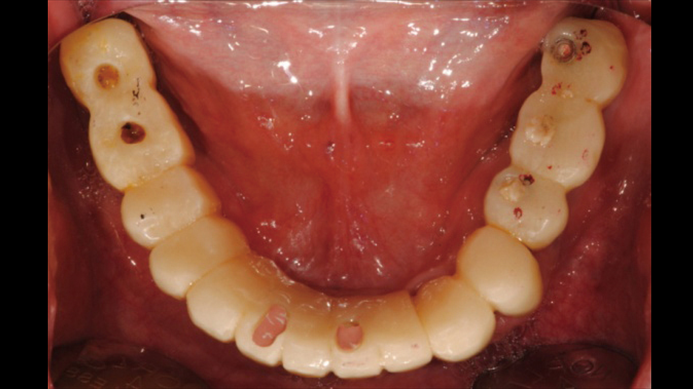

Clinical case: Full-mouth implants for mandibular & maxilla - restored using mixed prostheses

- Courtesy of Dr. Hyun Jun Kim, Korea -

Keywords

AnyRidge, full-mouth implants, mandibular, maxilla, edentulous, full mouth rehabilitation, Octa abutment, long-term clinical case, biological stability, Dr. Hyung Jun Kim

“AnyRidge ensures long-term biological stability

& functionality even in

full-mouth rehabilitation case. ”